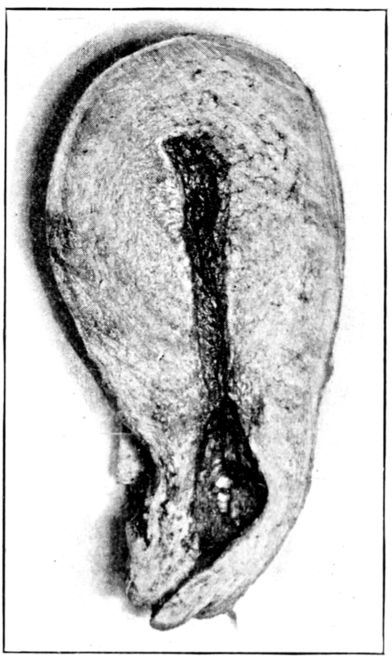

| 23. | Maternal surface of the placenta | 74 |

| 24. | Fetal surface of the placenta | 75 |